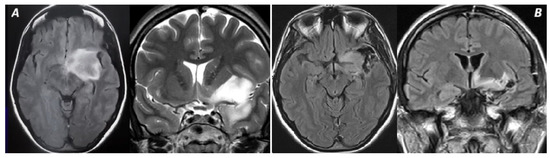

Figure 3. In this picture, a Kawaguchi grade 2 tumor is represented. (A) The invasion of LSAs and anterior perforated substance lead to the impossibility of performing a GTR, as shown in (B).

A GTR was achieved in 100% of B-S zone I tumors but only in 13.33% of giant lesions (p = 0.001) (Figure 1). Significant differences were noted between these groups and tumors located in the B-S I, I + IV, and I + II zones. The median EOR was 100% in Kawaguchi class 3 and 4 tumors but 86.5% in class 2 tumors (p = 0.032) (Figure 2 and Figure 3).